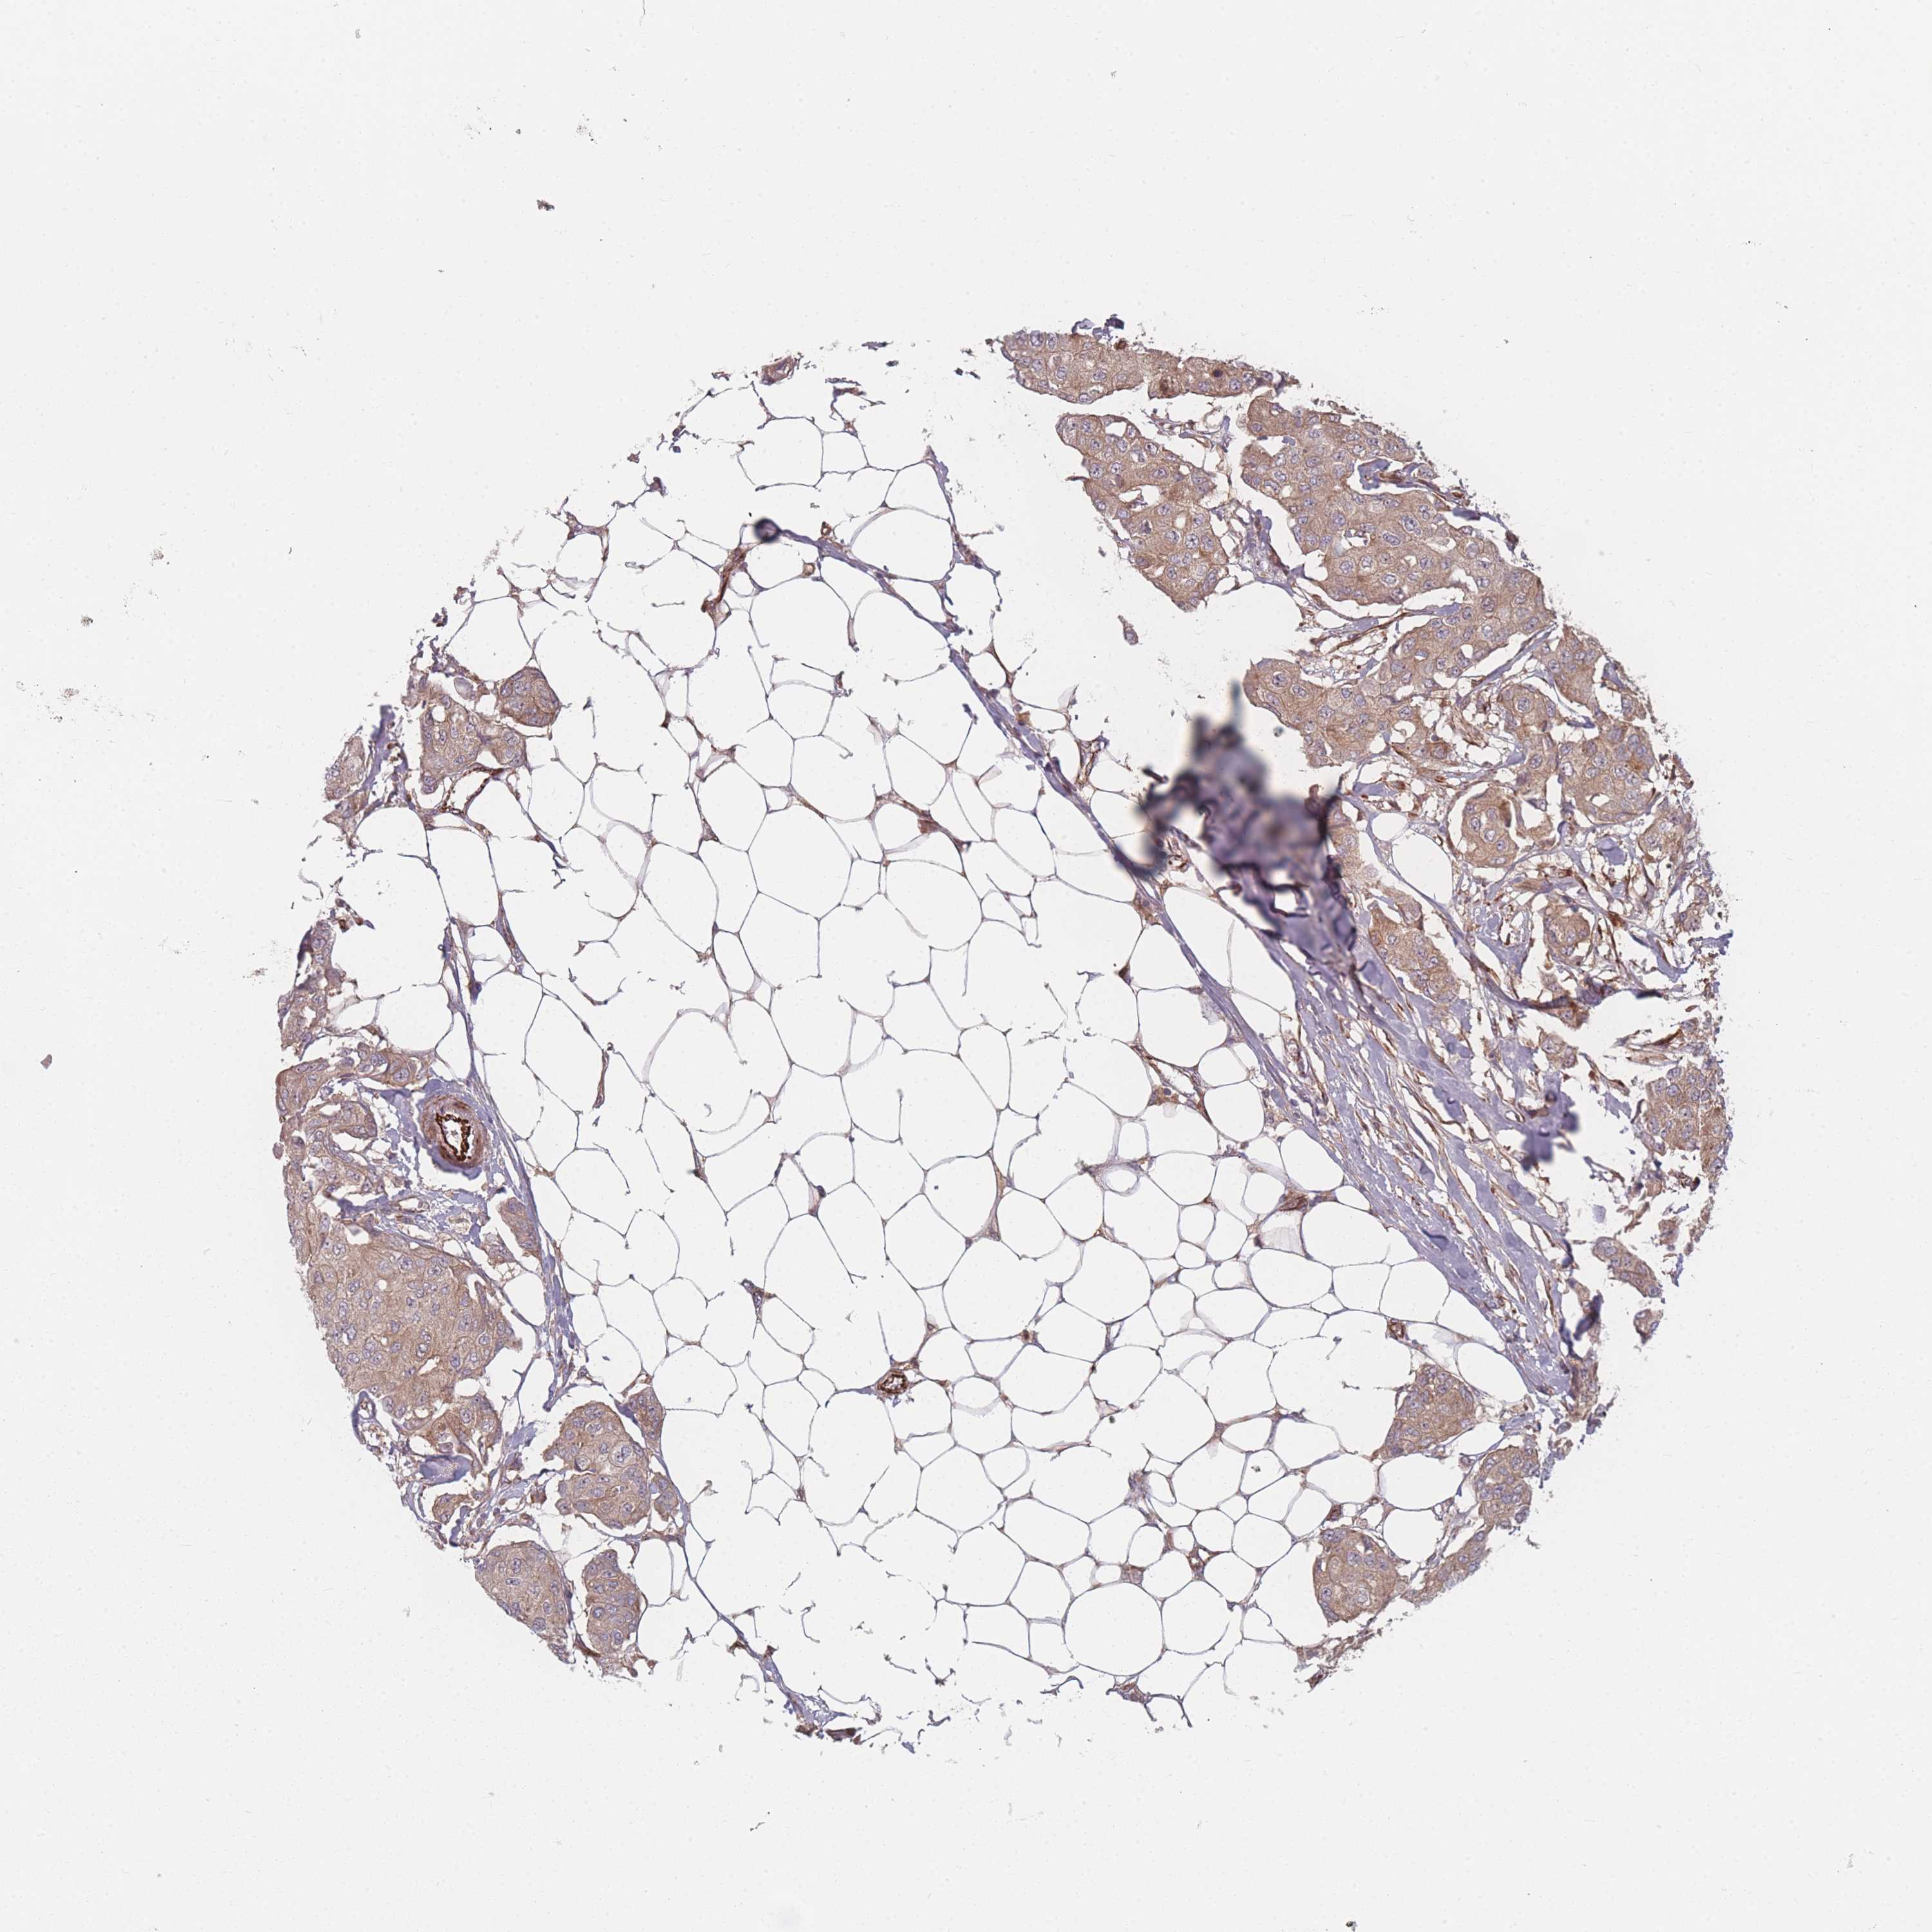

BRCA TCGA BRCA VALIDATION PROTEIN EXPRESSION

ANTIBODIES

AND

VALIDATION